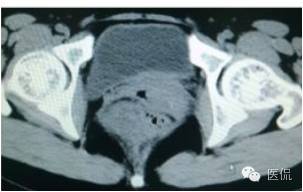

女,37岁,体检超声发现盆腔包块一周。无其他异常。

CT平扫(CT值23HU)